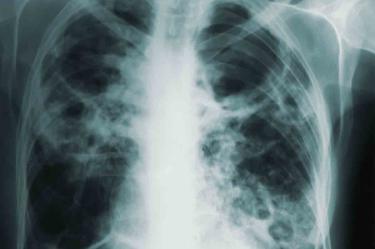

La neumonía está en el top 10 de las causas de muerte de las y los mexicanos, por eso en el Día Mundial contra la Neumonía, Adrián Rendón, especialista en neumología, llama a prevenir dicha enfermedad.

“La neumonía es una infección en el pulmón, las causas de esa infección son muchas, las más frecuentes son bacterias y los virus, ahora estamos muy familiarizados por el virus del covid como causa de neumonía, pero esto es un problema reciente; tradicionalmente los gérmenes que ocasionan la neumonía es uno muy conocido como el neumococo una bacteria, o el virus de la influenza, ahora se suma el del covid".